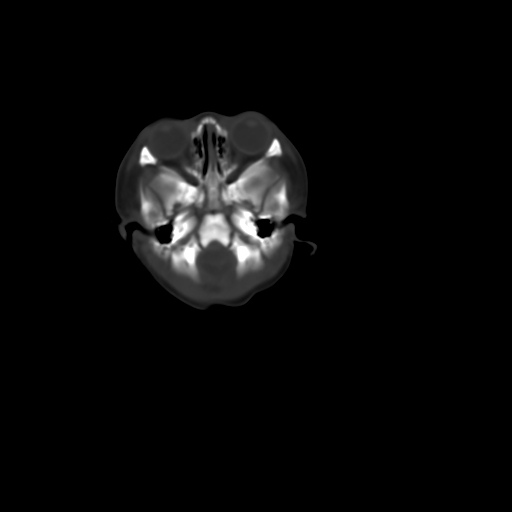

男,12天,自然分娩,其母发现右顶部头皮包块逐渐增大。

右顶部头皮血肿

右顶部头颅血肿(骨膜下血肿)

右顶骨呈膨胀性改变,骨纤维结构不良?

右顶部头皮血肿。

右顶部头皮血肿,可能是产道挤压所致。以后会慢慢恢复。

鉴别:骨膜下血肿,一般为产伤,应用产钳之类的吧

疑问:患儿脑白质密度比较低,基底节区密度比较高,类似于“双圈征”脑沟密度也偏高。该婴儿可有别的异常吗?反射正常吗?评分能达到5分吗?如果正常,就随诊观察吧。不正常要考虑到缺血缺氧性脑病。